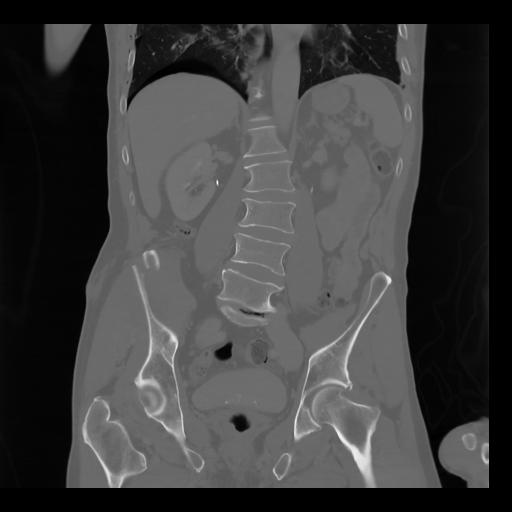

35 CUERPO,CE,Coronal,3.000,CUERPO,Coronal,